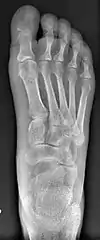

![]() Fig. 8a. Painful hallux valgus and metatarsus primus varus deformity recurrence of left foot after osteotomy surgery | |